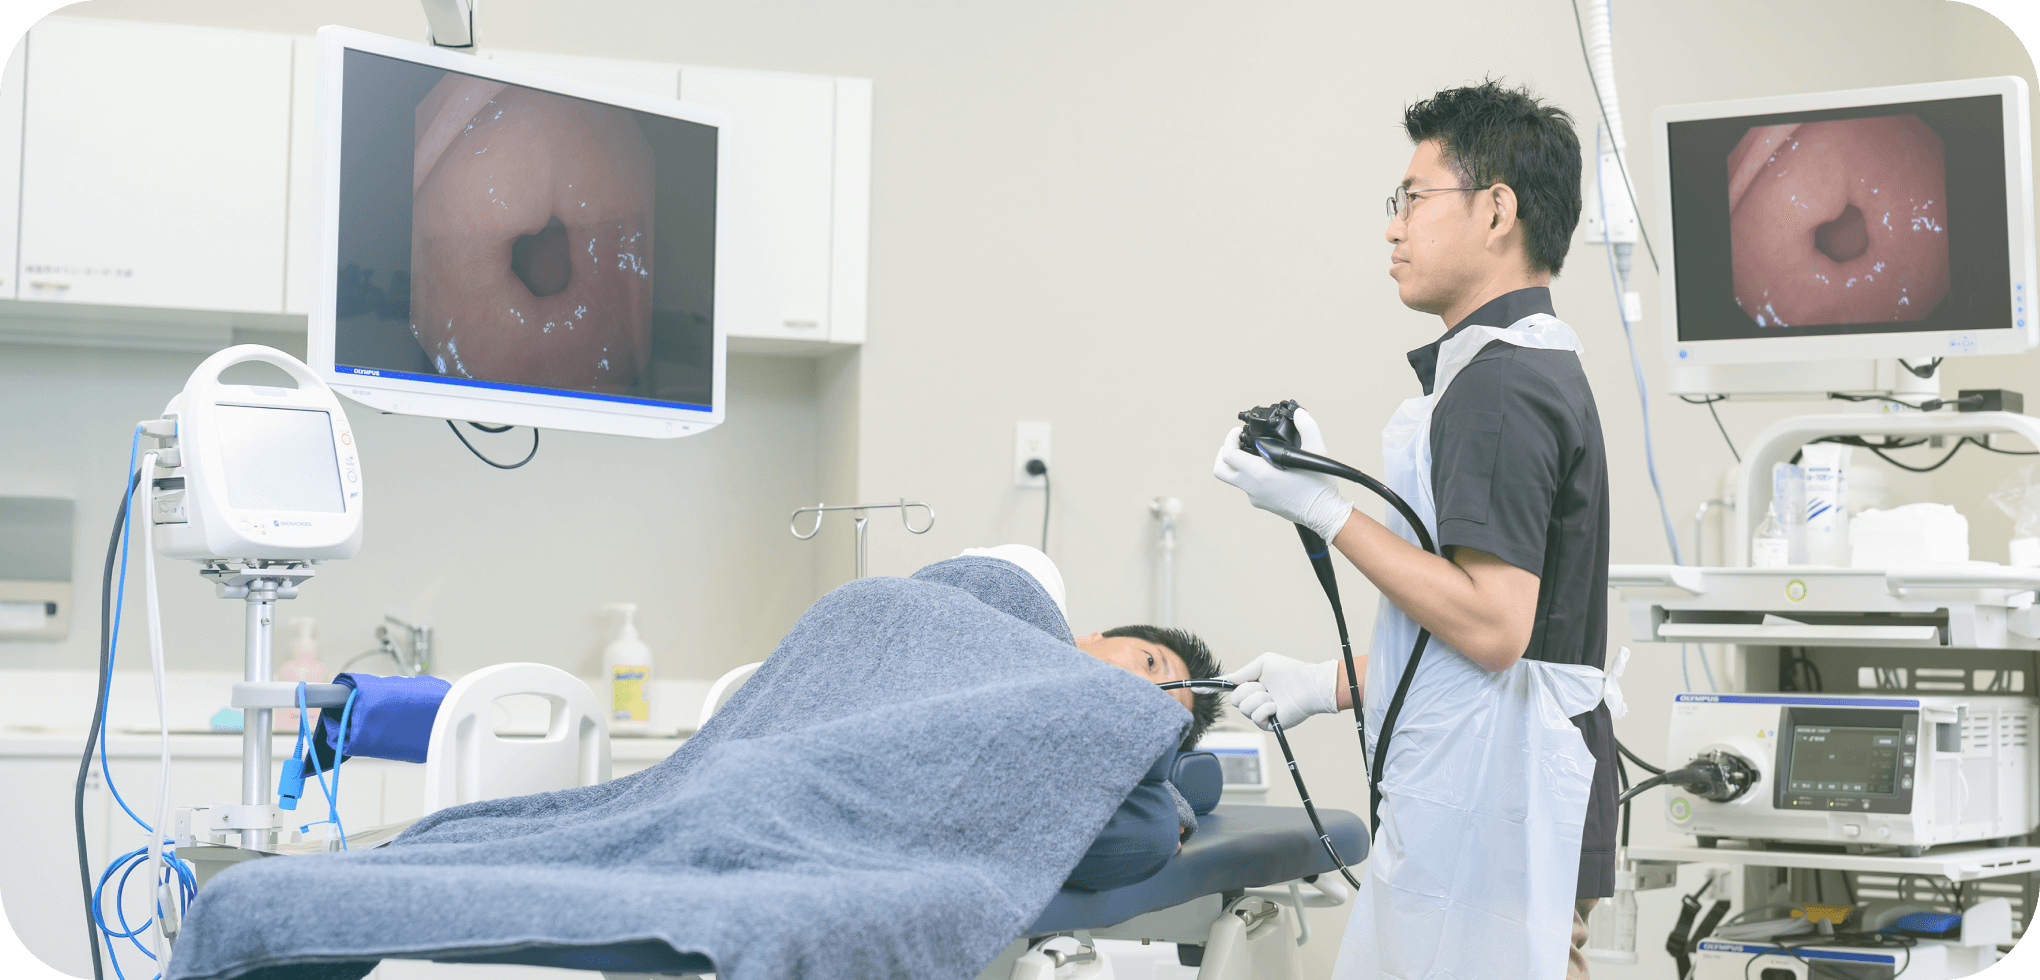

内視鏡のご案内

当院では、豊富な経験を持つ医師が高精度の胃カメラ検査および大腸カメラ検査を実施しております。鎮静剤の使用など、患者様の内視鏡検査による苦痛を最小限に抑える工夫をしておりますので、どうぞお気軽にご相談ください。